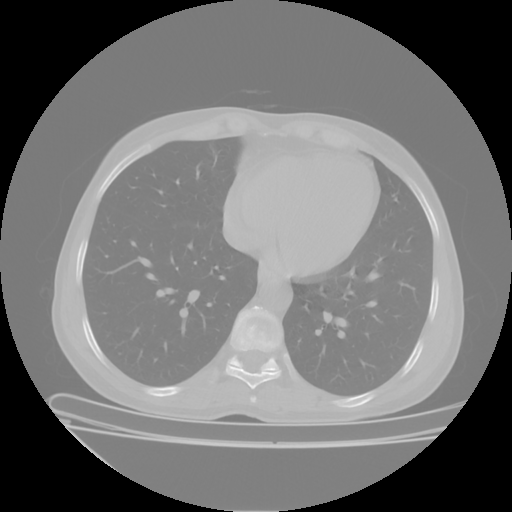

Targeted Slice 70 - Lung Window Analysis (Generated vs Real Venous)

0.609

Lung SSIM

106.8

Lung RMSE

53.6

Lung MAE

Average Lung Window Metrics Across All Slices (112 slices) - Generated vs Real Venous

0.626

Lung SSIM (Avg)

107.5

Lung RMSE (Avg)

51.7

Lung MAE (Avg)

Original NATIVE CT scan (input)

No window - Raw intensity values

Lung window (WL -600, WW 1500 β†’ Low βˆ’1350, High +150)